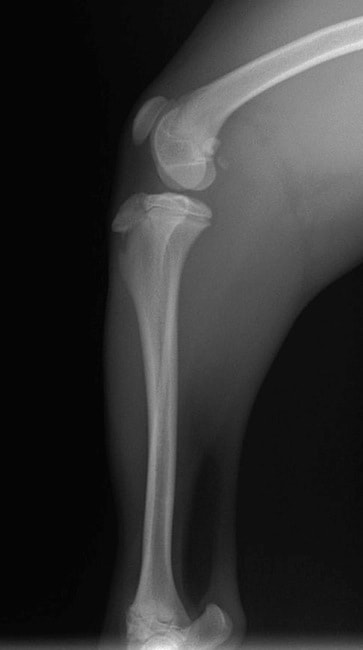

■ 症例22 ポメラニアン 1歳5か月 去勢雄

左後肢の挙上を主訴に来院した。整形学的検査、レントゲン検査より左右の膝蓋骨脱臼(左GradeⅡ〜Ⅲ、右Grade Ⅱ)を認めた。また、脛骨の前方引き出し試験の際に、引き出し兆候は認められないものの、疼痛が認められたため、前十字靭帯の損傷が疑われた。術中における、目視および関節内の操作によって、前十字靭帯の損傷や過伸展といった異常が認められなかったため、膝蓋骨脱臼の整復のみ実施した。手術手技は縫工筋及び内側広筋の解放、脛骨粗面の外側転位、滑車ブロック形造溝術、内外側関節包の縫縮を実施した。本症例は跛行もなく経過良好である。しかし、頸骨高平部の角度(TPA)が 右26.2°、左24.9°であり、解剖学的に前十字靭帯損傷のリスクが高いことから今後の経過に注意が必要である。